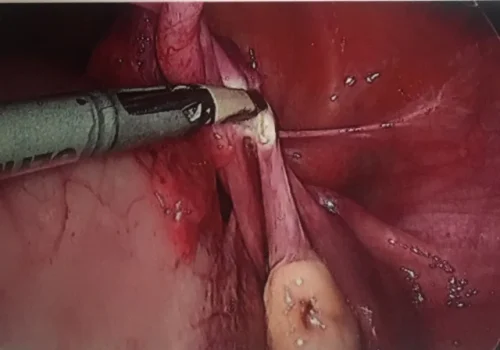

Procedure

She subsequently underwent Total Laparoscopic Hysterectomy.